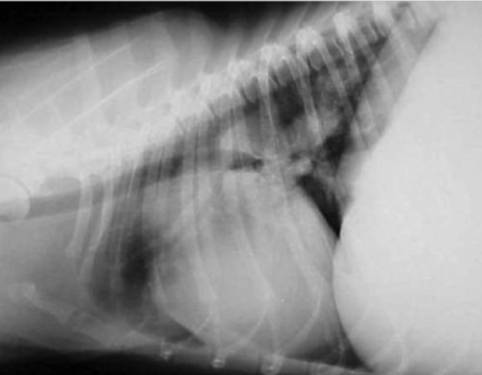

X线不能单独用来诊断心丝虫,但是可以判断疾病的严重程度,评估心肺的实质性变化。心丝虫病X线检测可见病变包括右心室肥大(图3),肺主动脉段突出,肺主动脉密度和大小增加,动脉弯曲。背腹位X片可观察肺后叶血管尺寸。如果血管直径大于第九肋骨直径,那么就是出现异常变化。左侧位X片可以评估肺前叶动脉,正常情况下其直径不能大于伴行的静脉或最接近的第四肋骨直径的三分之一(图4)。胸部X线还可检测肺部渗出物、结节、淋巴结及胸腔积液。肺实质变化包括肺泡间隙及肺泡的病变,特别是肺后叶会比较严重。另外,还会出现肺部嗜酸性肉芽肿。X线检测的变化可能是暂时性的,一般不能诊断为活跃的感染状态。

图4 心丝虫病例侧位片,可以看到肺动脉扩张。